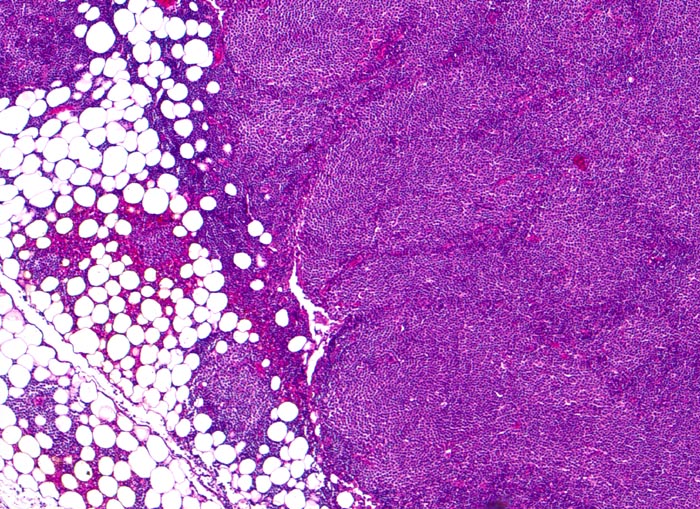

• Vergrösserter Lymphknoten mit zerstörter Lymphknotenarchitektur.

• Diffuse Infiltration des Lymphknotens durch monomorphe kleinlymphozytische Lymphomzellen.

• Unscharf begrenzte helle Areale (Proliferationszentren) auf dunkelblauem Hintergrund.

• Proliferationszentren (=Pseudofollikel) bestehend aus Lymphozyten und Paraimmunoblasten.

• Übergreifen des neoplastischen Infiltrates auf das umgebende Fettgewebe.